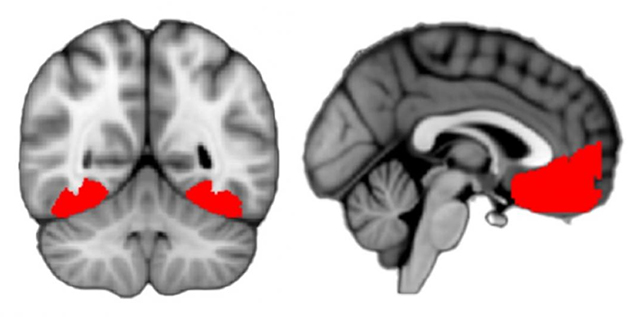

این رتبهبندیها به اسکنهای fMRI ارجاع داده شدند و فعالیت قابلتوجهی در سه ناحیه مشاهده شد: قشر پشتی-گیجگاهی (مرتبط با بینایی و تشخیص اشیا)، قشر جلوی پیشانی یا vmPFC (که ادراک ارزش و اعتماد را مدیریت میکند) و قشر سینگولیت قدامی (برای جمع آوری اطلاعات استفاده میشود).

به نظر میرسد vmPFC به عنوان نوعی پل عصبی قشر پشتی و گیجگاهی و احساسات ذهنی کنجکاوی عمل میکند؛ تقریباً مانند یک ماشه که به ما میگوید چه زمانی کنجکاو باشیم. هر چه داوطلبان نسبت به موضوع تصویر کمتر اعتماد داشتند، در مورد آن کنجکاوتر بودند.